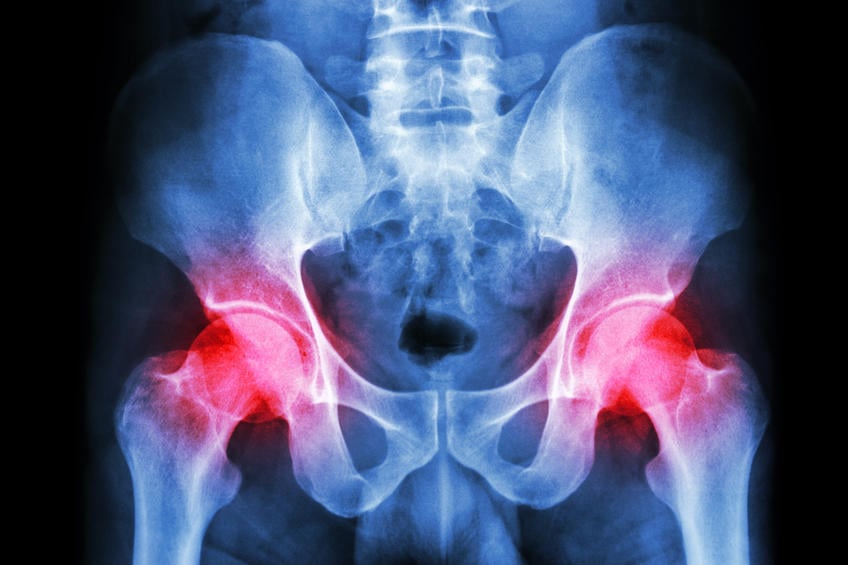

radiographie du pelvis et arthrite des deux côtés de l'articulation de la hanche (goutte, rhumatisme)

Istock

©iStock